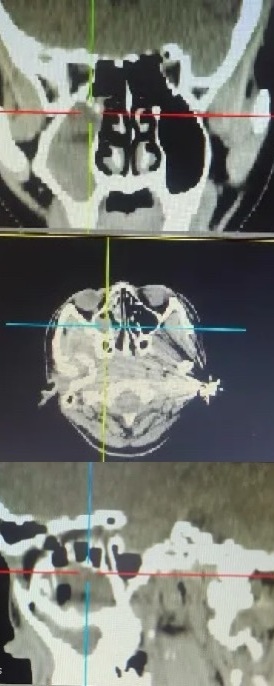

鼻内镜手术

通过鼻内镜进行鼻腔、鼻窦手术,具有创伤小、恢复快的优点。例如:鼻内镜鼻窦手术、鼻中隔偏曲矫正手术、鼻腔肿物切除术等。

鼻窦炎治疗成果展示

治疗前

治疗后